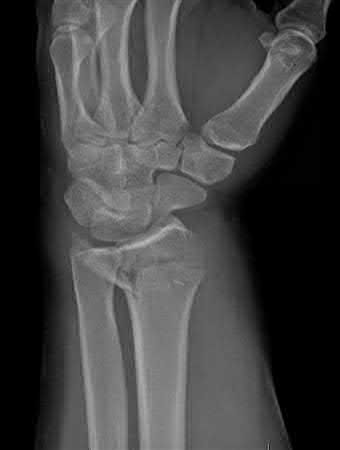

A 25-year-old male sustains an ankle fracture dislocation and undergoes open reduction and internal fixation. He returns to clinic five months following surgery complaining of continued ankle pain and instability with weight bearing. His immediate post-operative AP radiograph is seen in Figure A. Which of the following could have prevented this patient from developing persistent pain?

The patient presents with continued ankle pain and instability following open reduction and internal fixation. The radiograph in figure A demonstrates inadequate restoration of fibular length, likely leading to continued tibiotalar instability.

Illustration A demonstrates fibular malreduction with dislocation of the fibula anterior to the tibial incisura. Illustration B shows a comminuted fibula fracture along with a measurement of length from an intact fibula. The arc from the lateral process of the talus to the peroneal groove of the distal fibula is known as the "dime" sign and should remain unbroken if fibular length has been restored. Illustration C demonstrates the use of a push-pull screw and lamina spreader to regain length intraoperatively for a comminuted fibula fracture.

Chu and Weiner review management of malunions of the distal fibula. The authors state that restoration of fibular length, alignment and rotation leads to reduction of the talus, provides a buttress to talar motion in the setting of an incompetent deltoid, and allows the syndesmotic ligaments to heal at the appropriate tension.

Wikeroy et al conducted a study of patients from a prior prospective, randomized control trial comparing different methods of syndesmotic fixation. There was no significant difference in outcomes between tricortical or quadricortical 3.5mm screw fixation, however worse outcomes were seen with associated posterior malleolar fractures, obesity, a difference in sydesmotic width of 1.5mm or greater, and a CT confirmed tibio-fibular synostosis.

Sinha et al present a simple technique for fibular lengthening in the setting of distal fibula malunion. They found high union rates and improved AOFAS scores at short-term follow up with their technique.